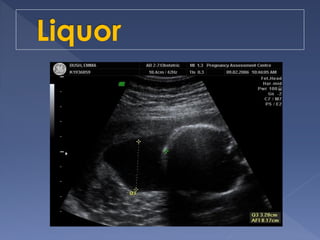

 Measure the dimensions of the largest

vertical pocket of amniotic fluid.

 Pocket of fluid

<1cm = oligohydramnios

1-2cm = decreased fluid

2-8cm = normal

>8cm = polyhydramnios

 Controversies in cut-off criteria for

oligohydramnios:

› < 0.5 mm

› < 1 cm

› < 2 cm

› < 3 cm

 Most reproducible/accurate

 Technique(4 quadrant technique)

Divide the uterus into four quadrants using the

linea nigra as the vertical axis and the

umbilicus as the horizontal axis.

 Linear transducer head placed along mother’s

longitudinal axis and held perpendicular to the

floor in the sagittal plane.

The pocket with the largest vertical dimension

is measured in each quadrant.

Sum of all four measurements = AFI

 Cord or extremities may traverse the

pocket, but may not be measured as

part of the vertical depth

 Values

<5cm = very low (oligohydramnios)

5-8cm = low

8-25cm = normal term AFI

>25cm = polyhydramnios